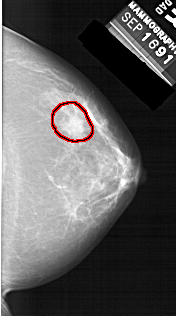

A_1456_1.LEFT_CC

LEFT_CC LINES 6136 PIXELS_PER_LINE 3076 BITS_PER_PIXEL 12 RESOLUTION 43.5 NON_OVERLAY

FILE: A_1456_1.RIGHT_CC.OVERLAY

TOTAL_ABNORMALITIES 1

ABNORMALITY 1

LESION_TYPE MASS SHAPE IRREGULAR MARGINS ILL_DEFINED

ASSESSMENT 4

SUBTLETY 2

PATHOLOGY BENIGN

TOTAL_OUTLINES 1

BOUNDARY